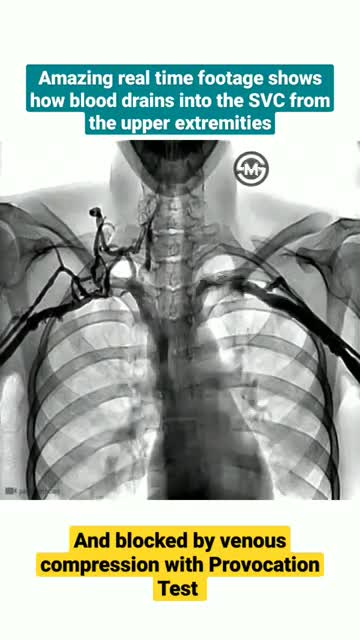

Real Time footage show how blood drains into the SVC from the upper exremities

Human body